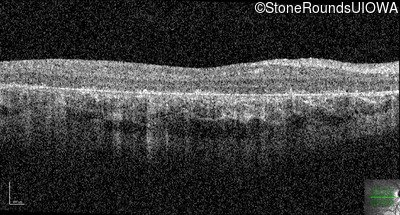

Age at visit: 9 years

Age at visit: 10 years